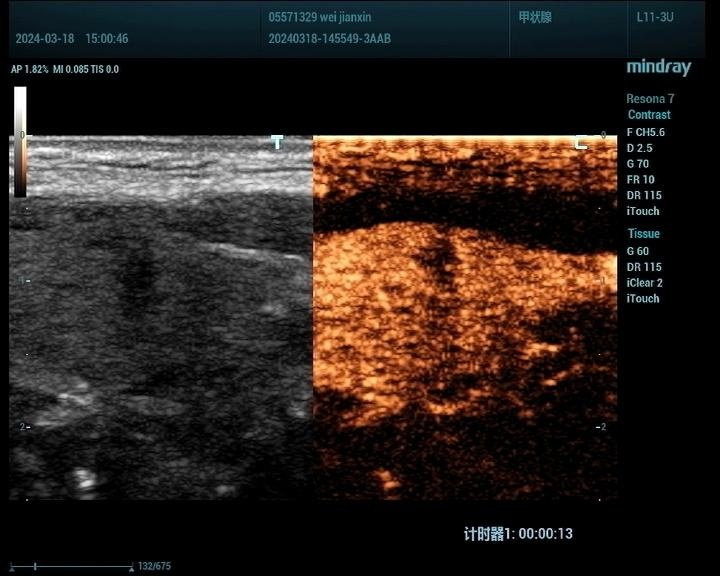

1、甲状腺:

观察甲状腺结节的血供情况:超声造影能够显示甲状腺结节的血供情况,有助于判断结节的活性及是否存在恶变倾向。

鉴别甲状腺结节的良恶性:通过超声造影,可以观察到结节的边界、形态、内部回声等特征,从而对结节的良恶性进行初步鉴别。

甲状腺癌病例